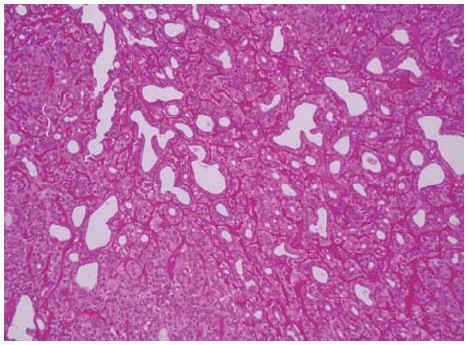

Se practicó una biopsia-extirpación de una de las lesiones, observándose en el estudio histopatológico con hematoxilina-eosina, varios islotes grandes hiperbasófilos y bien delimitados (no encapsulados) en la dermis reticular, sin conexión aparente con la epidermis. Éstos estaban formados por densas e irregulares trabéculas sólidas o tubuliformes en las que se distinguían dos tipos de células: unas periféricas con núcleo pequeño e hipercromático y otras centrales o periductales con núcleos grandes y pálidos (fig. 2), que contenían sustancia positiva al ácido peryódico de Schiff (PAS) resistente a la diastasa (fig. 3). Se realizó estudio inmunohistoquímico con antígenos CEA y EMA, proteína S-100, encontrando positividad para CEA y EMA.

Fig. 2.--Lóbulos epiteliales no encapsulados hiperbasófilos en dermis reticular sin conexión aparente con la epidermis. (Hematoxilina-eosina, ×10.)